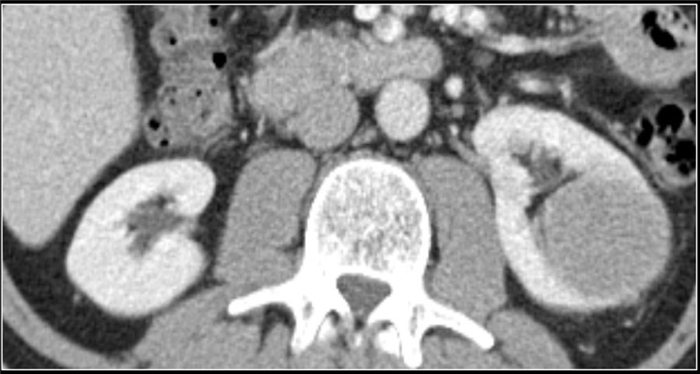

(Справа) КТ с контрастированием, аксиальная проекция: у мужчины 47 лет с остро возникшей болью в правом боку после мотоциклетной аварии выявлен травматический инфаркт правой почки вследствие тупой травмы. (Слева) КТ с контрастированием, аксиальная проекция: у мужчины 38 лет, получившего тупую травму из-за автокатастрофы, выявлен обширный инфаркт почки с отсутствием контрастирования. Обратите внимание на слабое контрастирование кортикального ободка.

(Справа) КТ с контрастированием, аксиальная проекция: у этого же пациента обнаружена только небольшая контрастируемая область левой почки. Выявлен тромбоз левой почечной артерии в результате травматического расслоения.